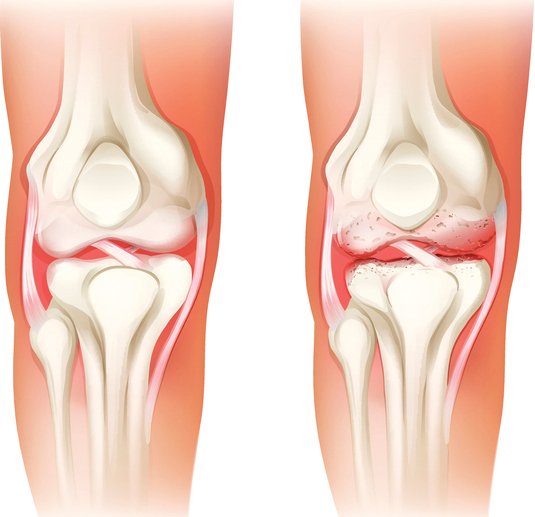

무릎의 연골도 대부분 관절과 동일하게 뼈를 매끄럽고 마찰이 덜가게 생성해 주는 미끄러운 연골 층으로 둘러 축적되어 있어요. 뿐 아니라, 무릎 중앙에는 부가적인 충격 흡수를 전달하는 반월상 연골이라고 하는 두 개의 고무질 반원형 연골 조각이 있어요.

뼈랑 뼈 사이에는 연골이 있어요. 연골이 망가진다는 소리는 뼈랑 뼈가 바로 닫게 된다는 소리 이라고 합니다. 그러면 통증이 발생하게 되죠. 무릎을 움직일 때 마다 통증이 생기고 불편해져요. 무릎 운동이 뻐근해지고 힘들어져요.